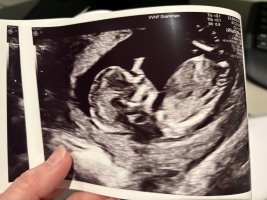

Sniker: jente![]()

Så kjekt! Takk for at dere sniker!Tipper også jente![]()

Alle har sagt jente, kanskje jeg må begynne å tro på det?

Ser ut som jenta vår, jeg tipper jente

Dette må da være en gutt?Noen som vil tolke denne? 15+4. Vis vedlegget 459049